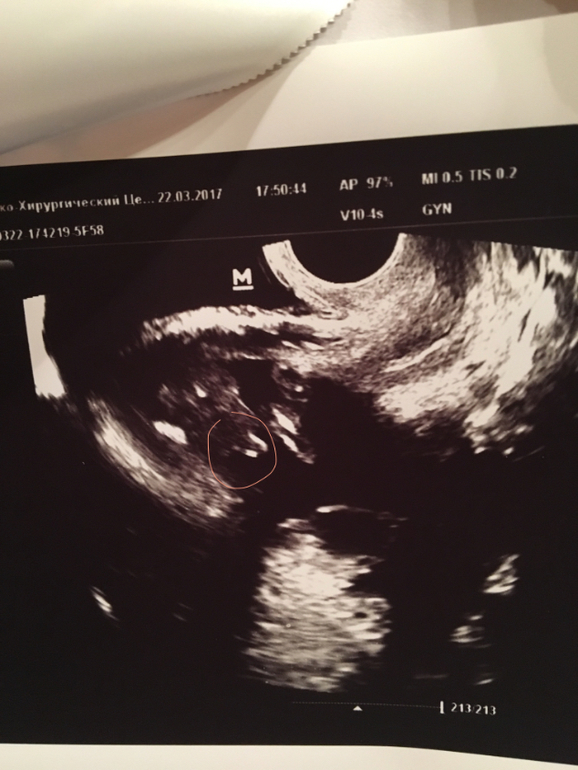

Мои неделькиПол малыша. Девочки, помогайте)))) мне ничего не понятно) фото под кат. Обвела то, что на мой взгляд показывает мальчик или девочка. П.С. На первом фото мне вообще ничего непонятно

Ну тогда зачем вы выставляете фото и интересуетесь? Я же вам и пишу, что на 17 неделе мальчика уже хорошо видно.

Фото головки есть? У девочек она гладенькая и кругленькая. У мальчиков более выпирающая и менее круглая.